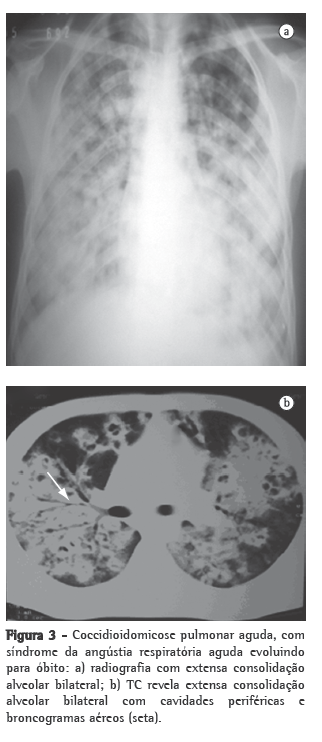

Os exames inespecíficos que são úteis para a avaliação do paciente incluem exames radiológicos e tomográficos, feitos nos sítios acometidos, principalmente no tórax, e podem auxiliar muito no diagnóstico (Figuras 2 e 3). As imagens mais frequentes ao radiograma torácico são nódulos pulmonares múltiplos de distribuição periférica, associados a consolidação parenquimatosa. Ao estudo tomográfico, os nódulos pulmonares periféricos mostram-se predominantemente escavados.(29,39)